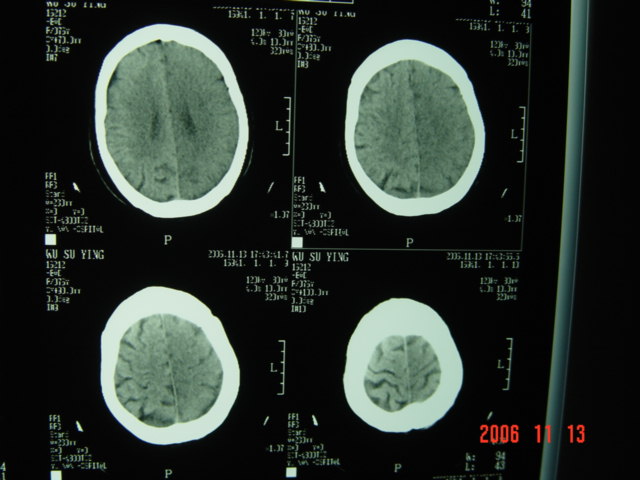

失语及右侧肢体无力3小时

左侧大脑半球与对侧相比较密度普遍密度降低,结合临床首先考虑是脑梗塞早期,必要时复查或mri。

左侧脑表面脑变窄,左外侧裂池受压变窄。

左侧侧裂池消失,脑沟变浅.典型的一侧大脑半球缺血改变.可以诊断:左侧大面积脑梗塞.

左侧大脑半球密度普遍降低,脑沟池消失,考虑大面积梗塞

左侧大脑半球大片密度减低影,脑沟变浅,外侧裂变窄,中线结构无明显移位。左侧大面积脑梗塞,大脑中动脉堵塞所致,愈后不好呀!应早期溶栓啊。

典型的左侧大脑半球缺血性脑梗塞早期表现[左侧大脑半球皮质密度减低与脑白质密度一致(脑皮质征),左侧豆状核轮廓模糊,密度与脑白质一致(豆状核征),结合临床有失语及右侧肢体无力3小时]。